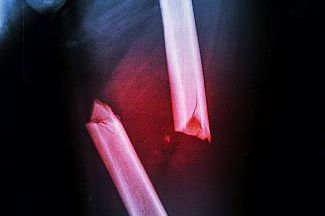

Wir bieten einte optimale und individuelle Therapie bei allen Verletzungen und ein umfangreiches Spektrum an unfallchirurgischen Operationen an. Die Klinik versorgt ambulant und stationär Arbeitsunfälle.